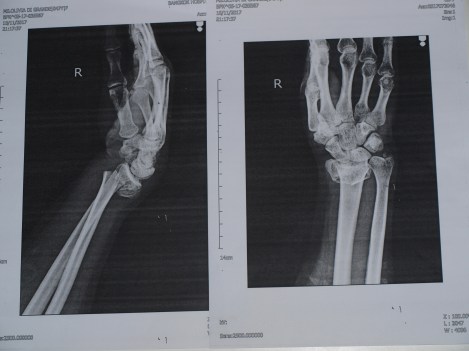

20:30 : Le diagnostic est confirmé et d’une certaine manière, il est pire que prévu. Triple fracture au niveau de l’articulation du poignet. Impossible de plâtrer, il faut opérer. Avec un peu de recul, l’opération est bien plus pertinente que le plâtre car la fameuse plaque de titanium permet de fonctionner  dès le départ avec une attelle.

J+4 : Impressionnant !!! Non ?